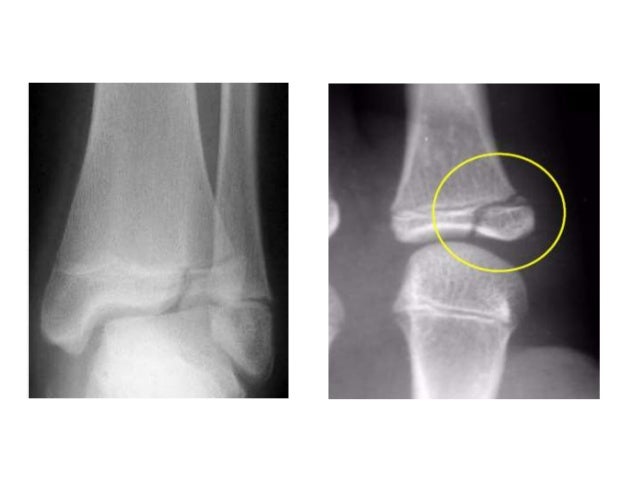

Fracturas

que afectan a las láminas epifisarias:

El centro de osificación primario del extremo superior de

la tibia aparece poco después del nacimiento y une el cuerpo de la tibia

durante la adolescencia (16-18 años).

Enfermedad de osgood-schlatter ;la rotura de la lámina

epifisaria en la tuberosidad de la tibia puede causar inflamación de esta y